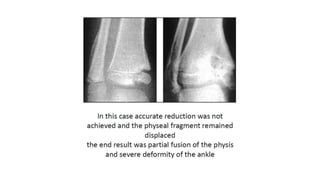

• A 7-year-old girl presented

with an ankle deformity

after a trampoline injury 7

months prior.

• MRI showing bony bars and

tethering of epiphysis and

metaphysis